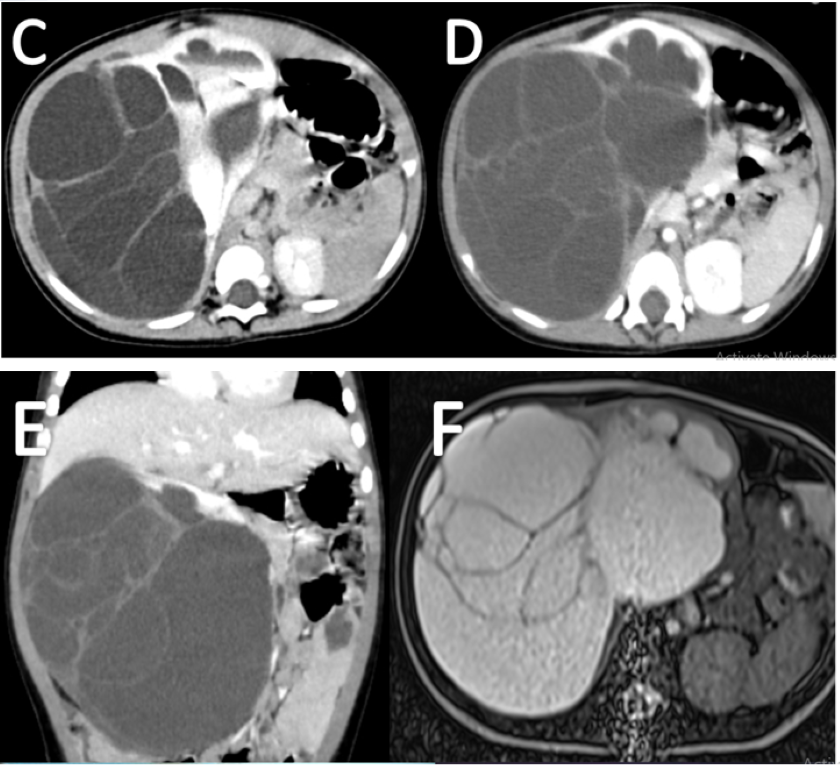

The patient was then operated, and mass was resected (Figure G) and sent for histopathology.

Histopathology reveals multiple variable-sized cystic spaces lined with cuboidal epithelium and hobnail cells (Figure H).

Figure G- Image shows gross specimen post-resection showing large well defined cystic lesion with the multilobulated surface.

Figure H- histology section from kidney illustrates multiple cysts separated by septae. The cysts are lined by cuboidal to hobnail cells. The stroma is composed of fibro collagenous tissue with oedema and mitotic changes.